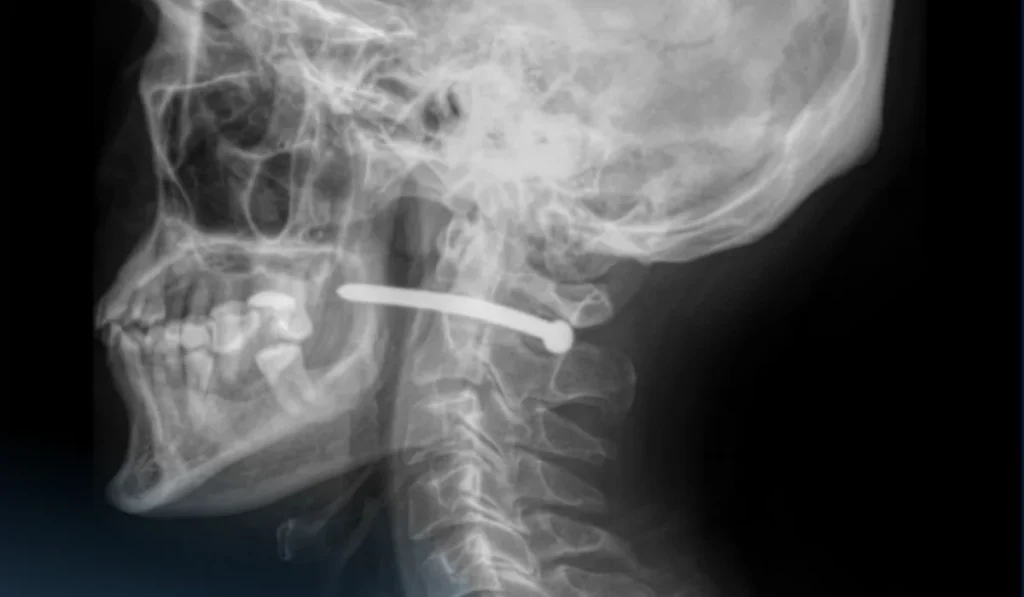

«Рентген-зерттеуден кейін шегенің омыртқаның мойын бөлігінен өткені анықталды. Ер адамның көрер жарығы бар екен – өміріне маңызды органдары зақым алған жоқ», — деп жазды аурухананың баспасөз қызметі.

Жақсүйек-бет хирургтары жарадан шегені алып, қарап, жараны өңдеді. Жара тігіліп, стерильді таңғыш салынғаннан кейін науқасқа ұсыныстар беріліп, үйіне жіберілді.

«Мойын тұзына жарақат алу өте қауіпті – мойынның маңайынан үлкен тамырлар, нервтер, тыныс алу жолдары және жұлын өтеді. Тіпті кішкене ғана зақым алудың салдары ауыр болуы мүмкін», — деп ескертті дәрігерлер.